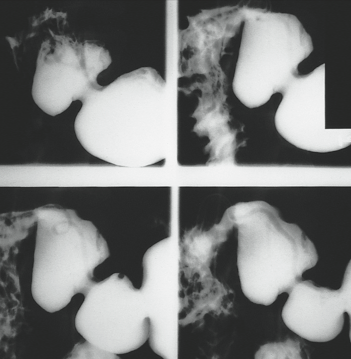

A 30-year-old woman had had no medical problems until she suffered a 4-week bout of coughing, wheezing, and fever while traveling in Indonesia. This was followed by diarrhea, nausea, vomiting, abdominal pain in the right upper quadrant, and anorexia. She returned to the United States, and her symptoms partially subsided. She sought no medical care at that time.

During a trip to Japan 3 years later, she had occasional attacks of diarrhea that contained bright red blood. This was attributed to external hemorrhoids. Returning to the United States about a year later, she continued to experience abdominal pain, nausea, and diarrhea. The following year, the diarrhea, nausea, and vomiting increased, and she lost weight. The diarrhea was worse at night, often awakening her.

The patient finally consulted a gastroenterologist 6 months later. Results of stool studies were negative for organisms, and findings from flexible sigmoidoscopy were within normal limits. Biopsy of the colonic mucosa revealed lymphoid aggregates. A subsequent upper GI series showed multiple ascarides in her stomach, duodenum, and small intestine. Within days, an esophagogastroduodenoscopy was performed but revealed no evidence of ascarides. The patient was treated with pyrantel pamoate, and her symptoms finally resolved.

Ascaris lumbricoides is harbored by 25% of the world population, including 4 million Americans. It is the largest nematode (15- to 45-cm long) that infects humans and is found predominantly in the jejunum, maintaining its position there with its intense muscular activity.

The typical A lumbricoides lives for 1 year, and each adult female produces about 200,000 eggs daily. Following fertilization, the eggs develop in moist soil before being ingested by the human host. The life cycle of these worms involves a 2-step process: an early, extraintestinal pulmonary phase followed by a prolonged intestinal phase. They hatch in the small intestine, then migrate through the intestinal wall and travel to the lungs via the bloodstream or lymphatics. About 10 days later, they ascend the tracheobronchial tree, are swallowed, and return to the small intestine to complete their maturation 14 days later.

A lumbricoides does not manifest itself clinically, but 3 clinical syndromes can occur. The pulmonary phase (4 to 16 days after ingestion) involves cough, fever, wheezing, dyspnea, and angioedema or urticaria. In the GI phase, patients have vague abdominal discomfort, colic, and occasional diarrhea. Complications of ascariasis include intestinal obstruction, usually in the ileum; not uncommonly, the worms migrate into the biliary ducts, producing a picture of acute cholangitis or hemorrhagic pancreatitis. Less frequent complications include appendicitis, intestinal perforation, peritonitis, liver abscess, and obstruction of the upper respiratory tract.

The diagnosis of A lumbricoides infection is usually made by demonstrating embryonated and unembryonated eggs and adult worms in the feces, although this patient’s stool studies were negative. In addition, an upper GI series with small bowel follow-up can be diagnostic—as it was in this case. After the patient’s bowel is emptied of barium, A lumbricoides may be identified by its barium-filled intestinal tract.

All patients who acquire worms need to be treated because of the danger of complications. Give pyrantel or mebendazole; piperazine is an inexpensive alternative. Do not use mebendazole or piperazine in pregnant women.

(Case and photographs courtesy of Drs Armand Cacciarelli, James Robilotti, and Emma Bell.)